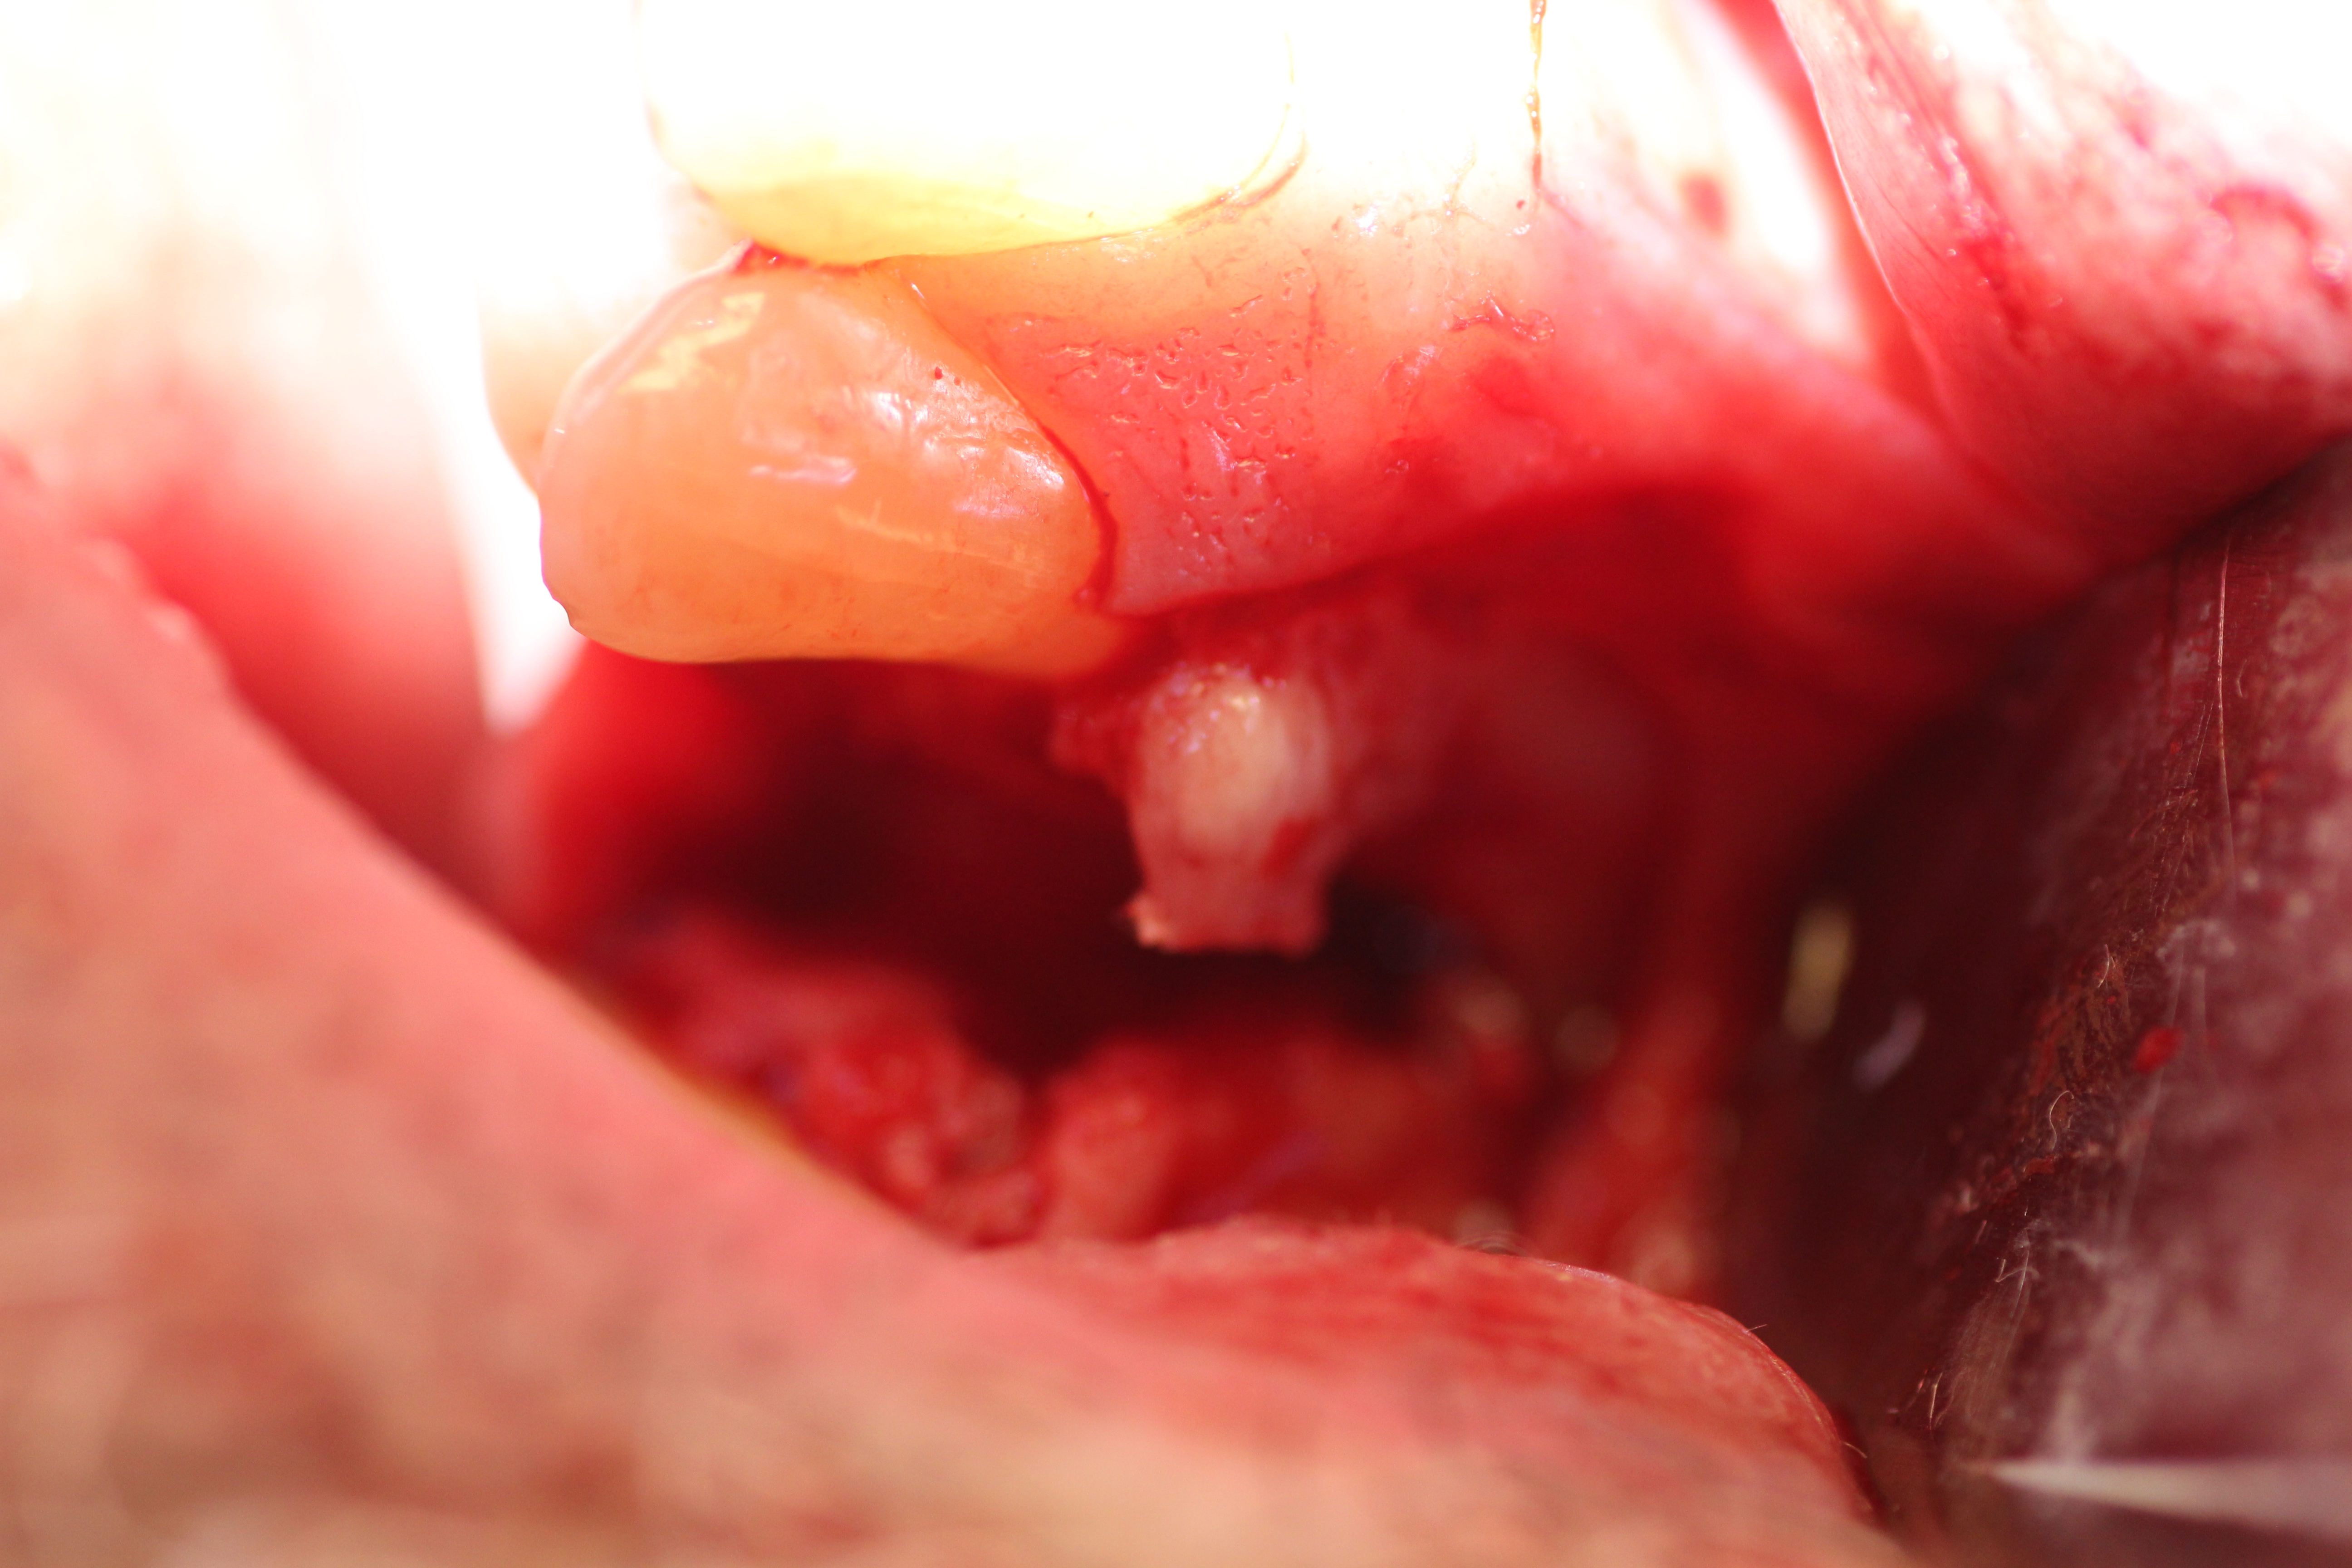

Case #3

Immediate placement with bone guided regeneration.

- Implant in place with mental nerve isolated.